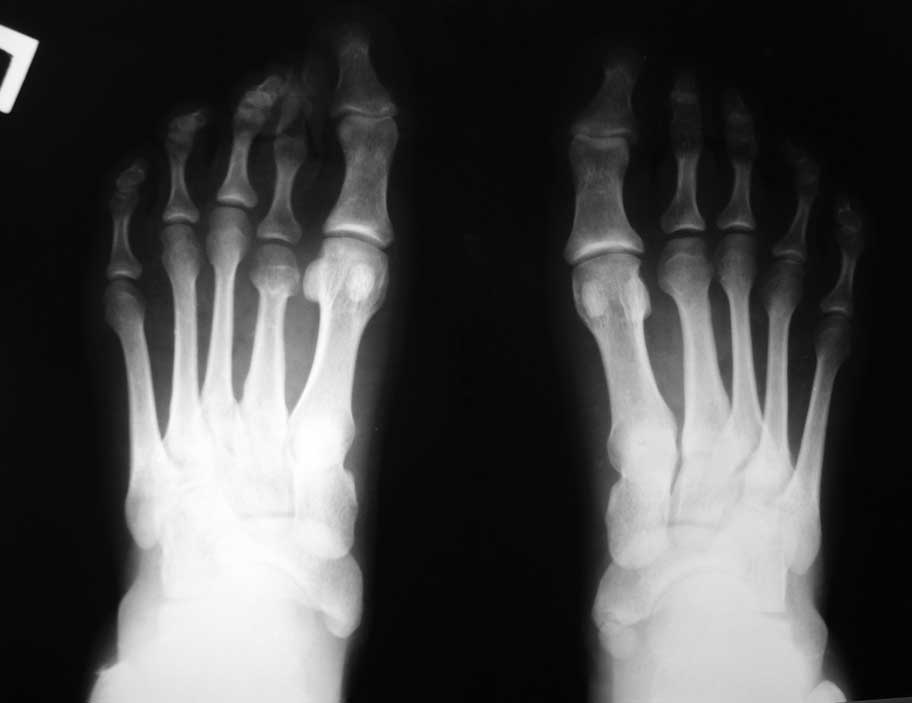

Вопрос об удлинении 2 плюсневой стоять не должен. Значительное утолщение ее диафиза и молоткообразная деформация 2 пальца свидетельствуют о функциональной перегрузке 2 луча. Удлинение 2 плюсны с большой степенью вероятности приведет к центральной метатарсалгии и прогрессированию деформации 2 пальца.

Как же тут можно говорить об укорочении 1 пальца? Укорочение относительно чего? Все зависит от точки отсчета. На мой взгляд, имеется избыточная длина 3 и 4 плюсневых. Подобную ситуацию можно назвать сложным нарушением формулы плюсневых костей. А вот про функциональные расстройства, за исключением помех при ношении обуви вследствие деформации 2 пальца, автор вопроса ничего не сказал.

Доктору Бережному С. Об укорочении 1 пальца за счет плюсневой кости можно говорить, сравнив ее длину по отношению к 3-5 плюсневым костям на ипси- и контрлатеральной конечности. На контрлатеральной конечности длина 3-5 плюсневых костей почти идентична длине плюсневых костей на стопе с брахиметатарсией. Поэтому говорить об избыточной длине 3-4 плюсневых костей как-то не очень. По поводу функциональных расстройств из-за брахиметатарсии, наверное, действительно, не особо следует. Правда возникает вопрос: а когда лучше - когда нагрузка равномерно распределяется на все 5 плюсневых костей, или когда всего лишь на четыре? Компенсировать же как-то надо недостающую опорную функцию укороченного пальца.

Я провел несколько ориентиров на представленных рентгенограммах, чтобы показать разницу в биомеханических ситуациях. На левой стопе перпендикуляр, проведенный к оси 2 плюсневой кости через дистальный конец 1 плюсневой (желтые линии) (принято за ориентир брать ось 2 плюсневой кости) проходит через верхушки 2 и 3 плюсневых. В нормальной ситуации 2 плюсневая кость должна быть чуть длинее 1-й. То есть на левой стопе можно говорить об относительно длинной 1 плюсневой кости. Именно этим объясняется наличие у молодой женщины признаков артроза 1 плюснефалангового сустава. А вот длина 4 плюсневой кости на левой стопе нормальная: перпендикуляр к оси 2 плюсневой проходит через середину латеральной сесамовидной кости и середину головки 4 плюсневой (красная линия). Теперь посмотрите на правую стопу: 3-я плюсневая кость намного длинее 1-й, а 4-я такой же длины. Такого в норме никак не может быть. А вот вторая при правильной разметке оказывается совсем чуть чуть короче первой. При этом абсолютная длина 1-й плюсневой (в милиметрах) у меня получилась на левой стопе даже больше, а длина 4 плюсневой на правой стопе на 4мм больше, чем на левой (голубые линии). Вот и получается, что на правой стопе наряду с небольшим укорочением 2 плюсневой есть более значимое относительное удлинение 3 и 4 плюсневых. И это в перспективе может быть причиной центральной метатарсалгии. Но пока жалобы пациентки связаны только с молоткообразной деформацией 2 пальца, лечение должно быть направлено на ее устранение наименее травматичным способом.

Лучше, когда на все равномерно. Но у данной больной удлинены 3 и 4 плюсневые. И значит на них, возможно, приходится избыточная нагрузка. К тому же еще раз обращаю Ваше внимание на толщину диафиза 2 плюсневой, которая свидетельствует о ее функциональной перегрузке. Возможно, ее головка расположена ниже остальных. Оценить расположение головок по переднезадним рентгенограммам мы не можем.

Что видим: укорочение 2 плюсневой кости, лёгкую молоткообразную деформацию 2 пальца, незначительное варусное отклонение 3 пальца. И всё! Длина 1 пальца, длины всех остальных плюсневых костей симметричны (померяйте с линейкой физическую длину – она отличается в пределах 2 мм, т. е. в пределах погрешности измерения и рентгенологической позиции). Hallux valgus’а нет никакого, даже interphalangeus (посмотрите на другую стопу). Диагноз: брахиметатарзия 2 плюсневой кости. Соответственно, нужно эту самую кость удлинять. А не укорачивать (разворачивать, отклонять) соседние кости!!! Этими вмешательствами даже теоретически невозможно решить проблемы пациентки, а ведь у каждой операции есть последствия и риски.